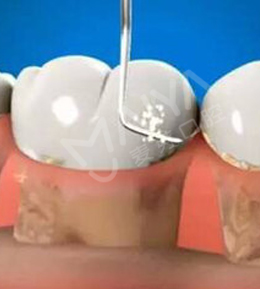

• 麦芽树脂补牙

麦芽树脂补牙即用无菌器械清除龋坏部分,清洗窝洞后用树脂材料进行填充,以恢复其外形和功能,对于严重的龋齿,需要进行根管治疗。

适应症:龋齿引起口臭